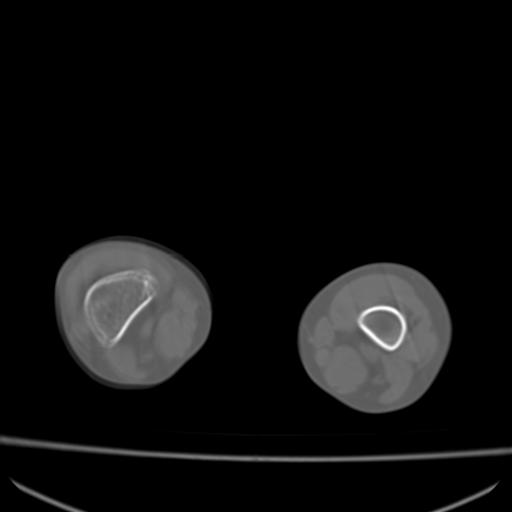

标题: PED0940:M12Y,左股骨下端酸痛畸形 [打印本页]

标题: PED0940:M12Y,左股骨下端酸痛畸形

12岁男孩,左膝关节肿痛8年,近月明显

内生骨软骨瘤?

血友性关节病?